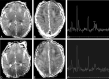

Results: In most of the patients a characteristic evolution of DTI and MR spectroscopy parameters was seen during the first 2 weeks after birth. Although the anatomic images were normal or nearly normal on the first 2 days after birth in most patients, abnormalities were detected on DTI (both visually and by quantitative interrogation of D(av) maps) and proton MR spectroscopy (abnormal metabolite ratios). These parameters tended to worsen until about day 5 and then normalize, though in several patients abnormal metabolite ratios persisted. Of interest, as areas of abnormal diffusivity pseudonormalized within one region of the brain they would develop in other areas. Therefore, the pattern of injury looked very different when imaging was performed at different times during this evolution.

Conclusion: Patterns of injury detected by standard anatomic imaging sequences, DTI sequences, and proton MR spectroscopy varied considerably during the first 2 weeks after injury. The appearance of new areas of reduced diffusion simultaneous with the pseudonormalization of areas that had reduced diffusion at earlier times can result in an entirely different pattern of injury on diffusivity maps acquired at different time points. Awareness of these evolving patterns is essential if studies are performed and interpreted during this critical period of time.